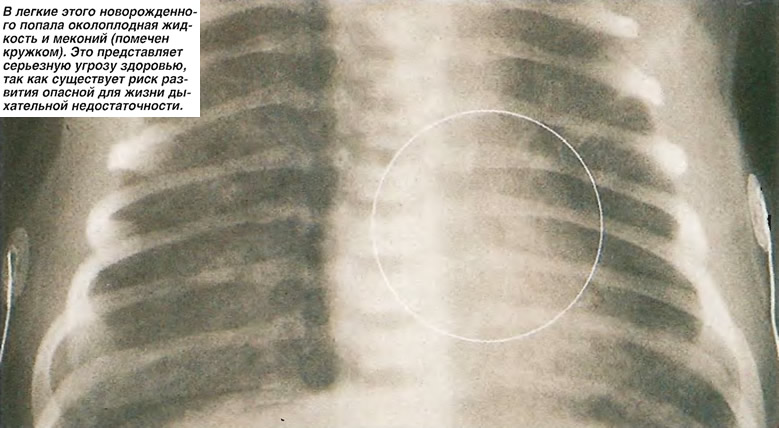

Медицинские аспекты мекония в околоплодных водах

Раздел: Мудрость в объективе